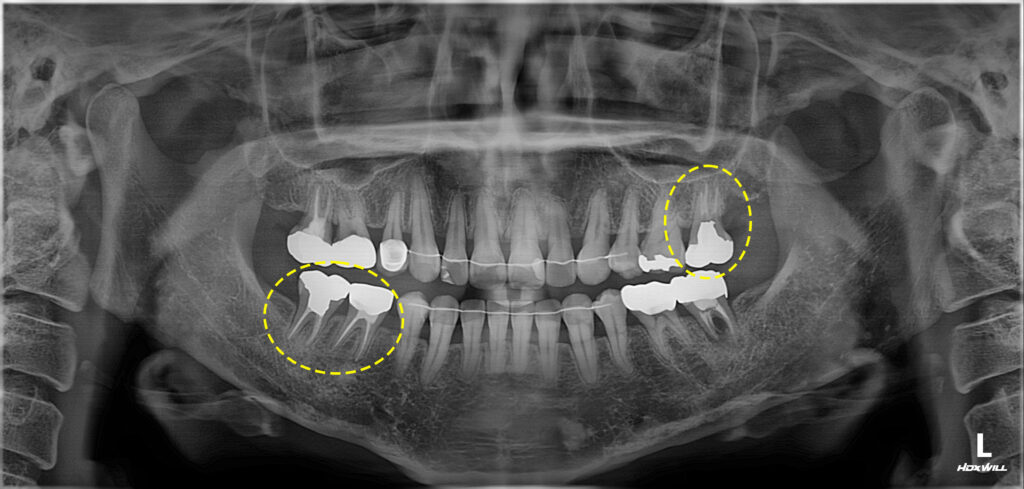

환자분께서는 치아 사이 공간이 있어서

교체를 원하신다며 내원해 주셨는데요.

사보험을 가지고 계셨기 때문에 연간 3개의

크라운 혜택이 적용 가능하셔서 오른쪽 아래

어금니 부위 교체를 먼저 진행하기로 하였습니다.

이어서 2024년에 왼쪽 위 가장 안쪽 어금니에

통증이 있어 타 치과에서 재신경치료가 어렵다고 하여

발치권고를 받으셨으나 광화문치과에서

재신경치료를 진행하셨는데요.

왼쪽 아래 임플란트까지 모든 치료를

마무리하였는데요.